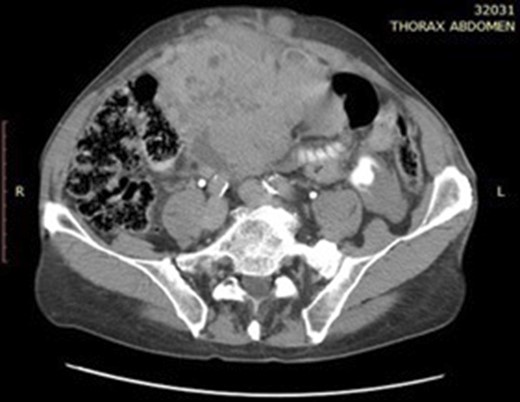

A 72-year-old gentleman presented to our unit with a recurrent mass of the anterior abdominal wall. This mass appeared gradually over several months causing a dull pain. No other symptoms were described. Clinical examination revealed a 11 × 10 cm soft and well defined, palpable mass on the right side of the abdominal wall (Fig. 1). Computer tomography (CT) of the abdomen presented several space-occupying lesions in the peritoneal cavity, the right side of the lower pelvis and the rectovesical pouch, measuring 11 × 10.4 × 10.7 cm, 8 × 6.5 cm and 7.5 × 5.7 cm, respectively (Figs 2 and 3). Due to compression, the veins of the anterior abdominal wall presented dilated. Thorax CT scan revealed no tumour.

Abdominal CT scan showing two hypervascular lesions in the abdomen.